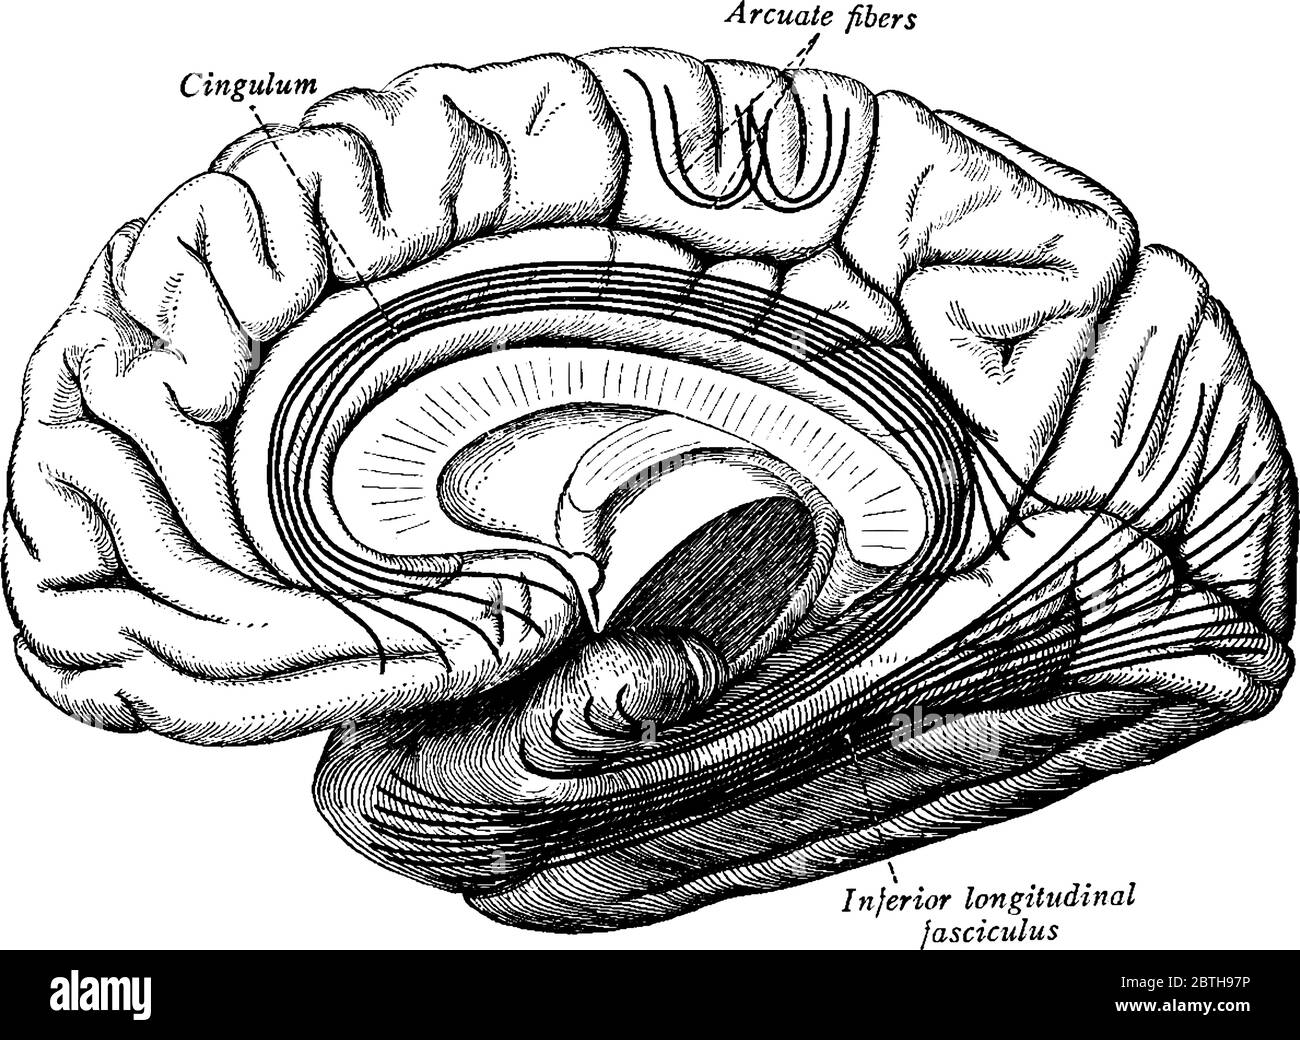

RF2BTH97P–Una rappresentazione tipica della corteccia cerebrale, i tratti di associazione più importanti del cervello. Le fibre sono proiettate sul mesiale (mediale)

RF2B74CND–I tratti di associazione più importanti del cervello, disegno di linea vintage o illustrazione di incisione.